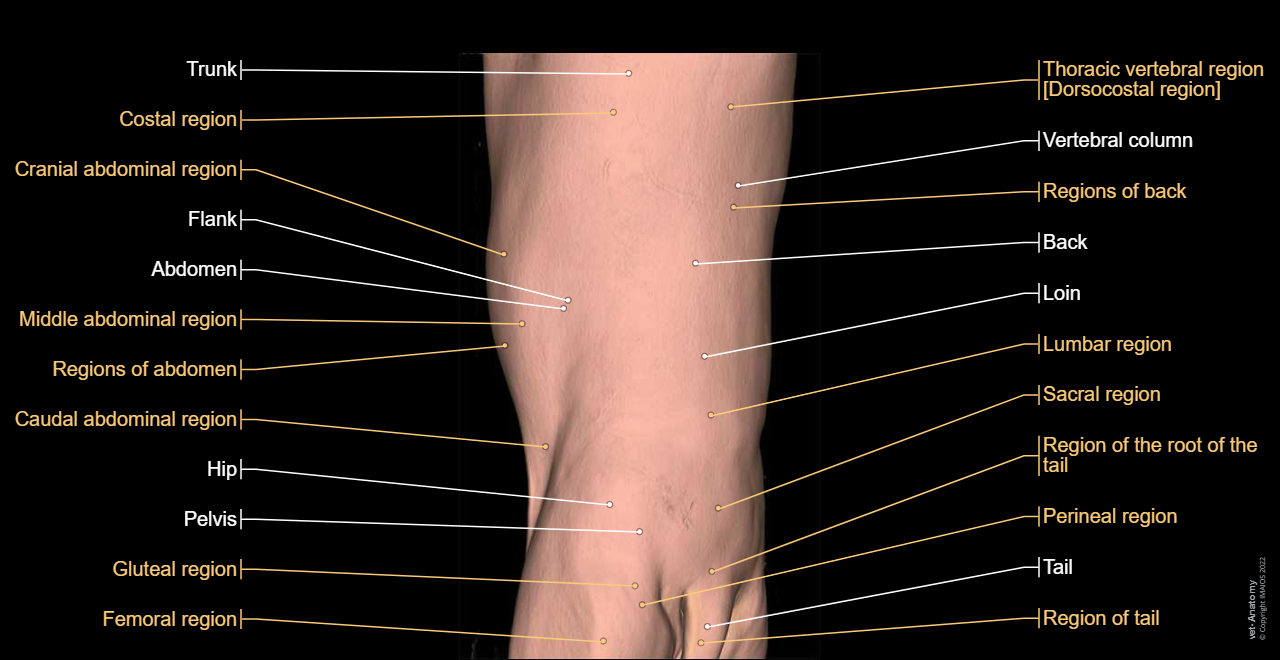

Surface anatomy - 3D: Trunk (Dog)

Surface anatomy